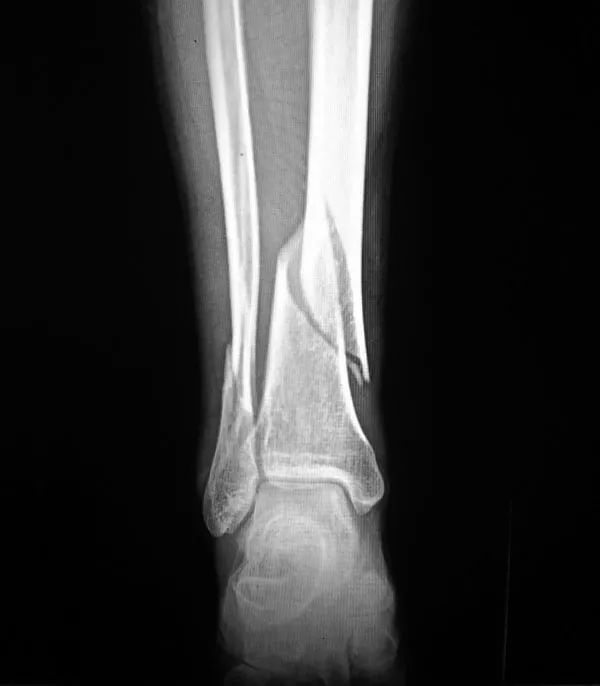

2、骨折:骨質(zhì)疏松癥最常見(jiàn)的并發(fā)癥是骨折,輕微外力即可導(dǎo)致骨折,60歲以上老年人骨質(zhì)疏松并發(fā)骨折者高達(dá)12%。多見(jiàn)咳嗽打噴嚏時(shí)、彎腰屈伸撿東西、回頭轉(zhuǎn)身及摔倒等易發(fā)生骨折。骨量丟失20%以上時(shí)易發(fā)生骨折,輕者可使活動(dòng)受限,重者須長(zhǎng)期臥床,給社會(huì)和家人造成很大負(fù)擔(dān)。老年人骨折可引發(fā)或加重心腦血管并發(fā)癥,導(dǎo)致肺感染和褥瘡等多種并發(fā)癥的發(fā)生,嚴(yán)重危害老年人的身體健康,甚至危及生命,死亡率可達(dá)10%~20%。